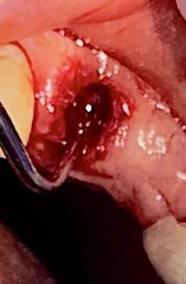

Sindesmotomía con un periostótomo de molt # 9, posteriormente se realizó la luxación con un elevador recto, buscando el punto de apoyo, seguido se efectuó la prensión con el fórceps 150 en el diente con sumo cuidado de no tocar la encía colocándolo hasta el cuello dental, haciendo movimientos de lateralidad y rotación hasta lograr la dilatación del alveolo, y finalmente la tracción del órgano dentario, observando que la raíz este integra, y que estructuras alrededor estén conservadas, de la misma forma se revisó el alveolo en busca de la presencia de granulomas o espículas óseas, una vez ya revisado se procedió al curetaje, con una cucharilla de lucas, se introdujo y se dio paso al retiro del exudado purulento, se realizó irrigación del alveolo con solución fisiológica, una vez limpio se realizó una sutura simple con sutura nylon, seda # 3/0 en el medio del alveolo con la finalidad de aproximar rebordes, evitar su contaminación por el ingreso de comida, además generar una mejor cicatrización en una zona estética , finalmente se aplicó presión por medio de una gasa que mordió el paciente por un lapso de 30 minutos, para contribuir con una hemostasia adecuada.

Figura 6. Sindesmotomía, luxación y prensión del incisivo lateral superior derecho pieza N.º 1.2

Elaboración: Los autores.